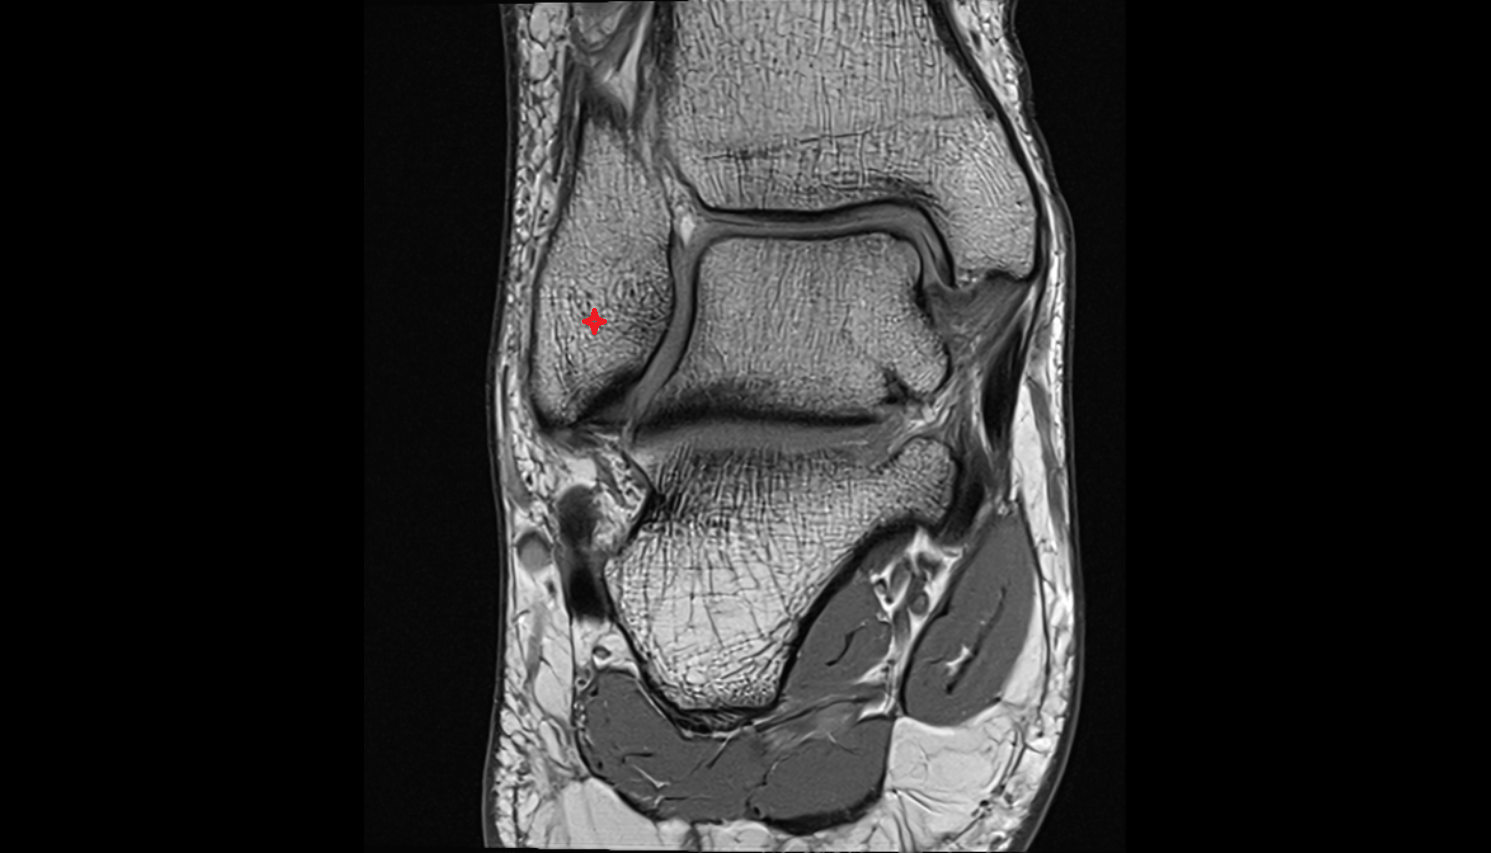

- Knee Joint